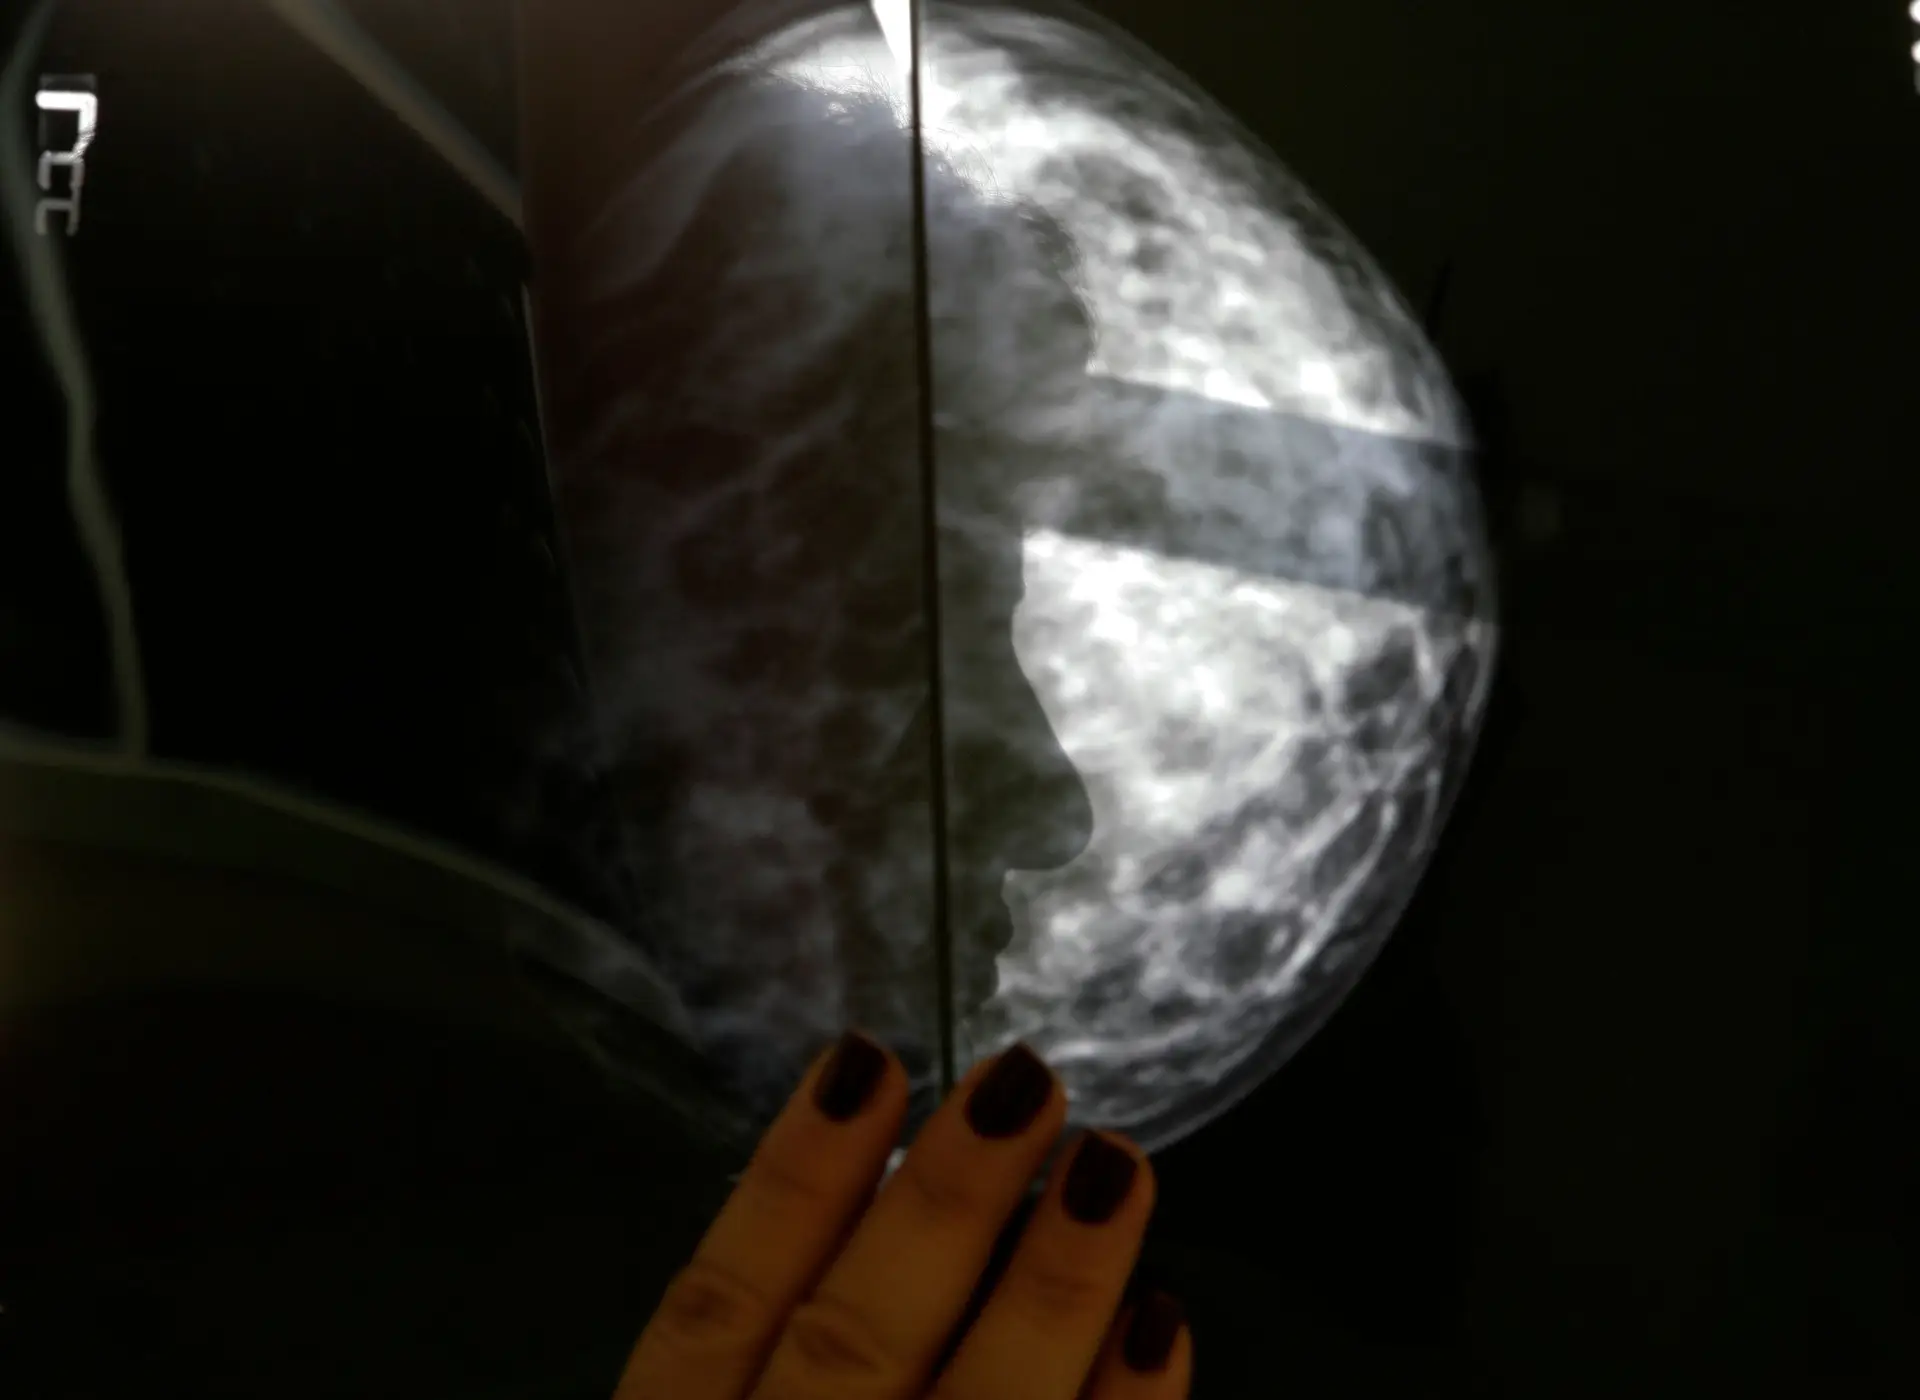

O rastreio gratuito do cancro da mama é alargado, nos próximos dois anos, aos distritos de Lisboa e Setúbal, podendo beneficiar, no total, 600 mil mulheres, na região sul, até 2023 , anuncia hoje em comunicado a Liga Portuguesa Contra o Cancro (LPCC)

Com esta iniciativa, as mulheres dos distritos de Lisboa e de Setúbal passam a contar com a melhor qualidade do diagnóstico nesta área, possibilitada por equipas técnicas especializadas e equipamentos digitais novos.

Esta iniciativa partiu do Núcleo Regional do Sul da Liga Portuguesa Contra o Cancro, em 1997, e foi-se alargando gradualmente ao longo do tempo, tendo já sido realizadas cerca de cinco milhões de mamografias em todo o país e um milhão, na região sul.